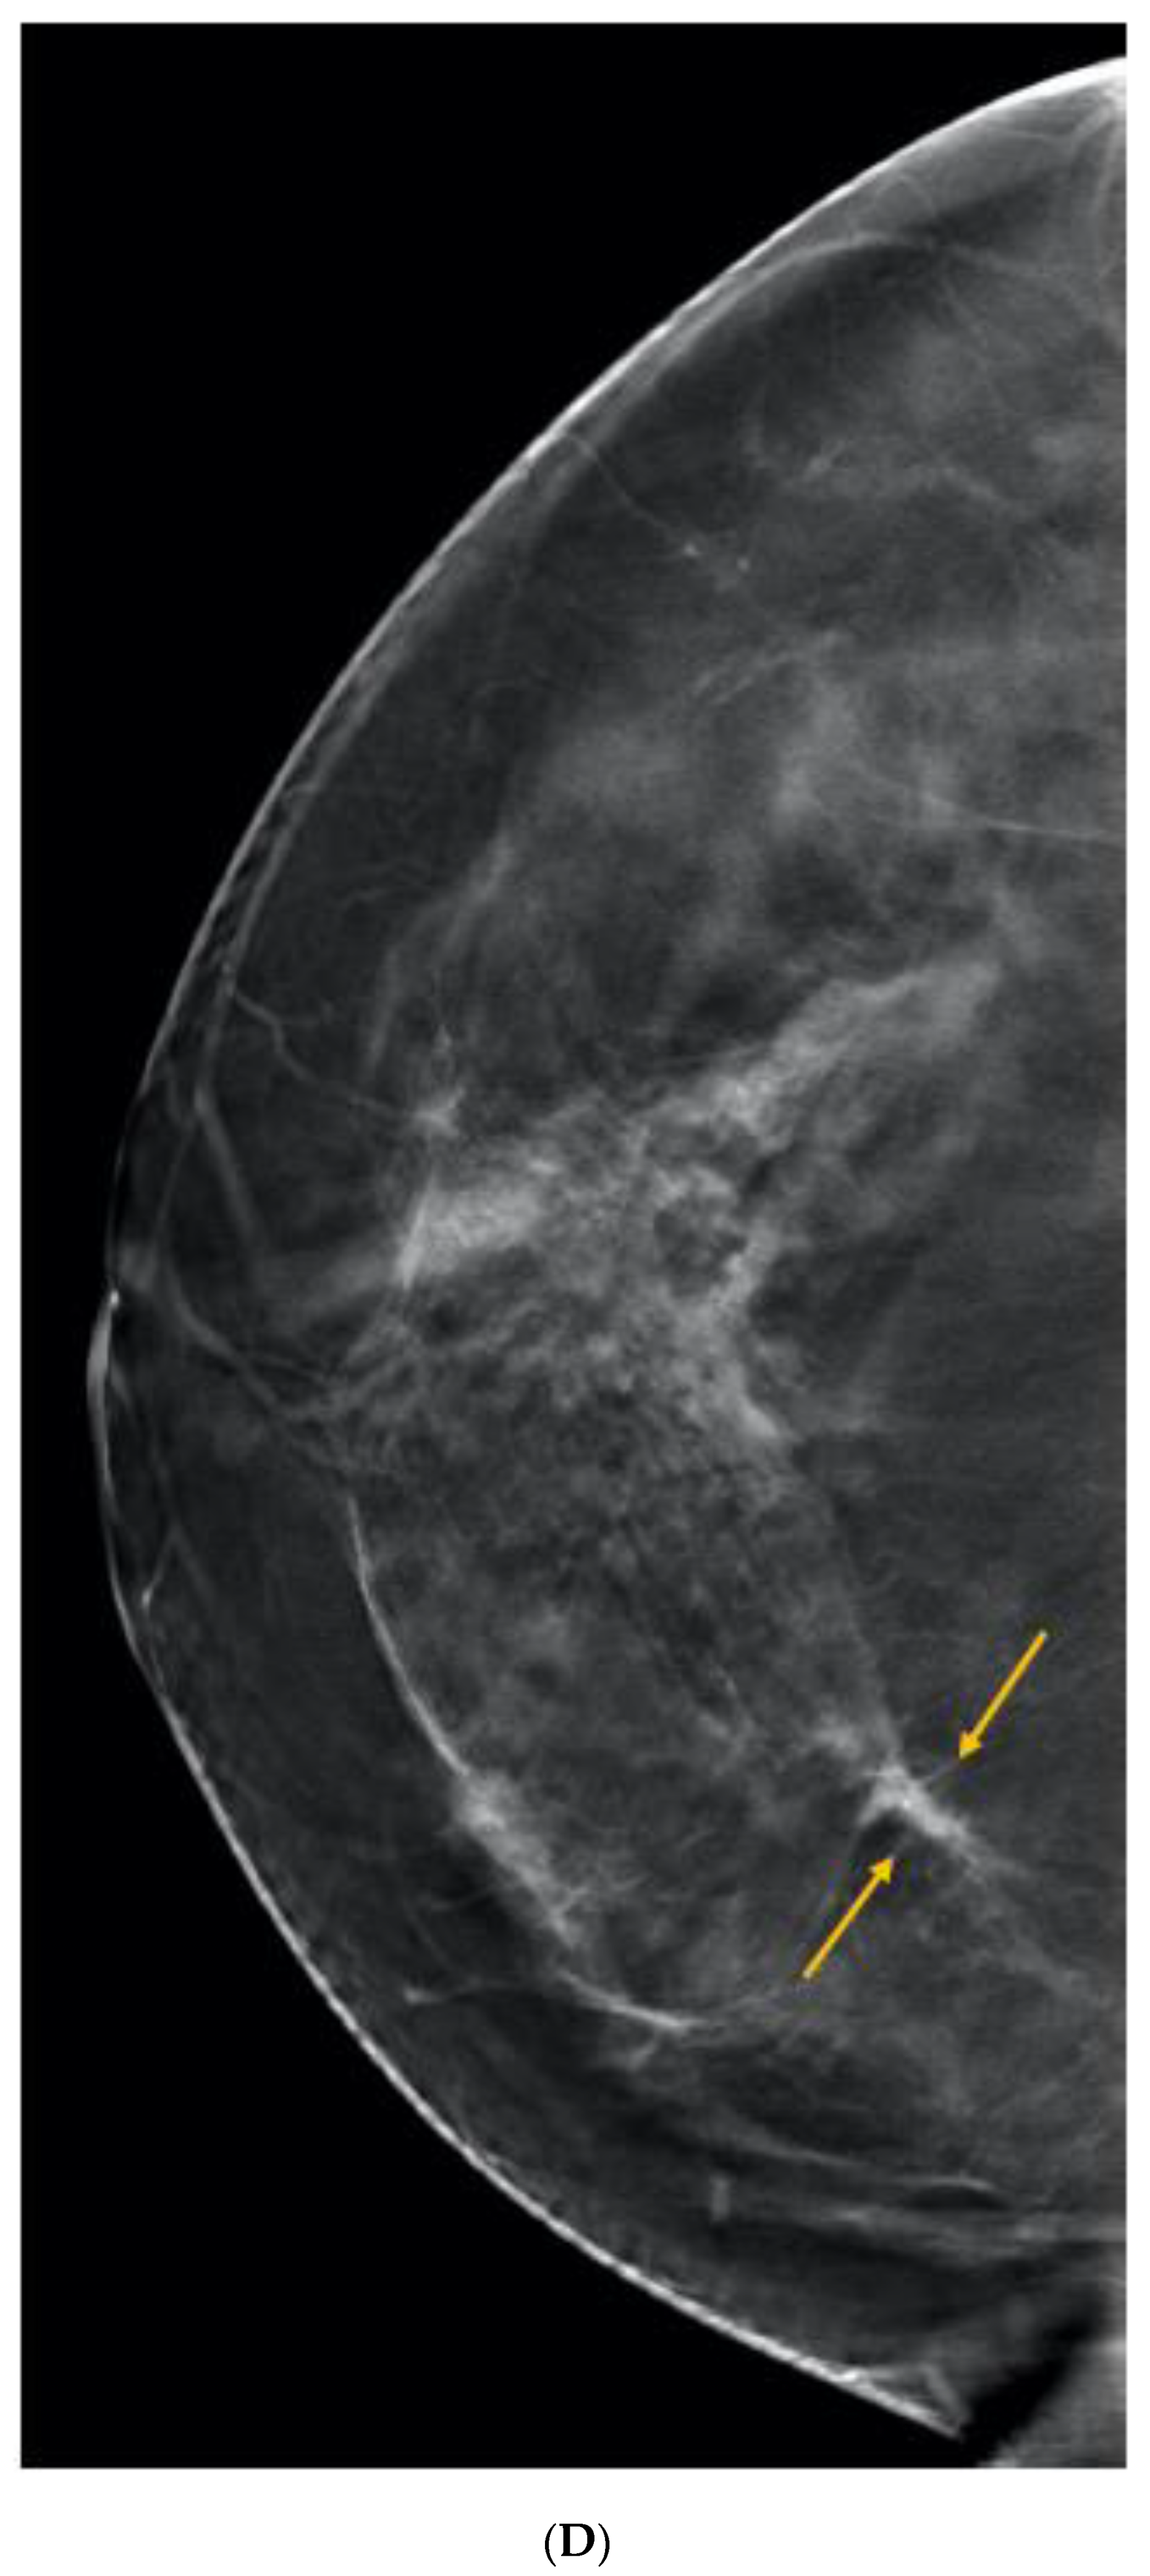

6. Digital Breast Tomosynthesis (DBT)